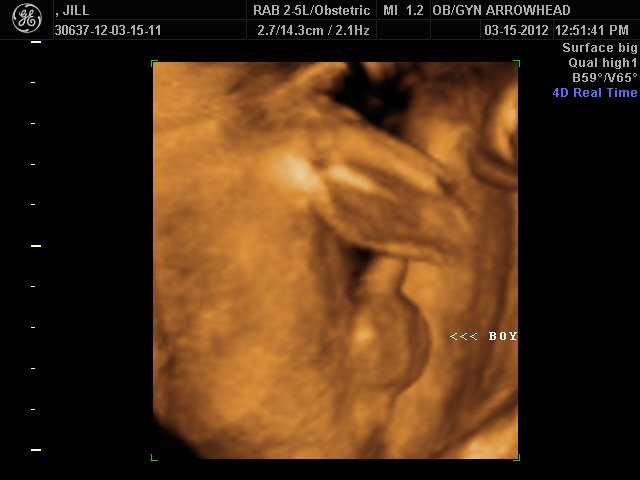

We offer complimentary 3D/4D Ultrasounds to all our OB patients around 30 weeks! The following photos are some examples of our work, shown with permission from our patients.